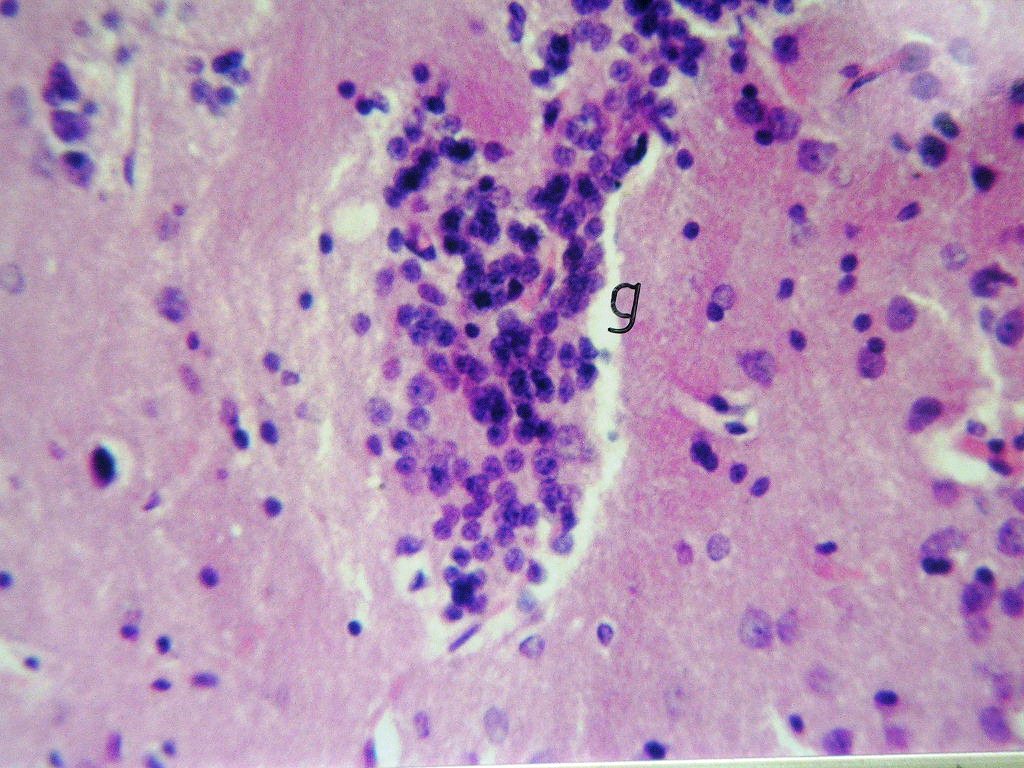

Fig (1): Micrograph of brain section of normal control rat showing normal morphological structure of the hippocampus (H& E X40). Fig (2): Micrograph of brain section of ovariectomized control rats showing normal morphological structure of the hippocampus (H& E X 40). Fig (3): Micrograph of brain section of Al-intoxicated ovariectomized (AD group) rats showing various sizes of amyloid plaques formation (arrow) in the cerebral cortex and hippocampus (H& E X 40). Fig (4): Micrograph of brain section of AD rats treated with α-chymotrypcin in a dose of (8.1 unit/rat/day) showed the presence of focal gliosis in the cerebrum and disappearance of most of amyloid plaques.

Fig. 4: Micrograph of brain Section of AD rats treated with α-chymotrypcin in a dose of (8.1 unit/rat/day) showed the presence of focal gliosis in the cerebrum associated with the disappearance of most of amyloid plaques.